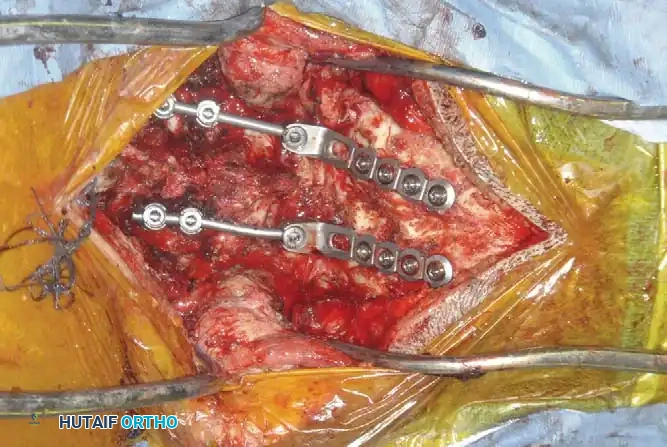

Fig 6. Anterior cervical plating construct providing rigid stabilization of the anterior column.

Posterior Cervical Fusion (PCF) and Instrumentation

Indications: Posterior tension band failure, irreducible facet dislocations requiring open reduction, or multi-level instability.